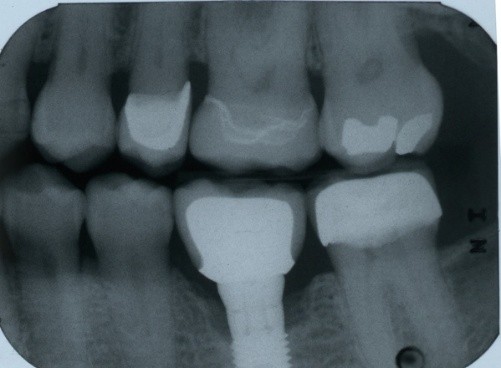

13. (Select ONE or MORE correct answer)

Which of the following is true regarding dental implant at site 2.6?

14. (Select ONE OR MORE correct answer)

Which of the following is true regarding dental implant at site 3.6?

15. (Select ONE or MORE correct answer)

16. (Select ONE OR MORE correct answer)

There is radiographic evidence of

Regarding dental implant at site 3.6, there is evidence of